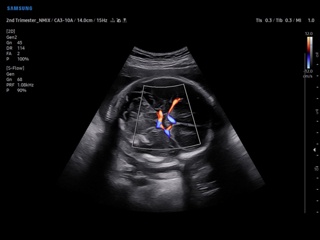

В разделе "Акушерство" атласа представлены результаты ультразвуковых исследований беременных на разных сроках. Здесь вы можете посмотреть изображения внутренних органов, мозга, сердца и пола плода, эхограммы многоплодной беременности, кровотока в плаценте и пуповине, пороков развития и др.